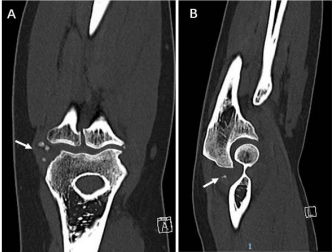

A 44year-old woman presented with limitation of right elbow motion and progressively worsening with pain associated elbow movements. The pain was present when the patient was at rest, and aggravated when the elbow in motions. She did not describe any swelling but with catching, locking symptoms. The pain was started six-years ago after fell over accidently on an outstretched hand. After the accident she visited at emergency department and radiological imaging did not revealed any abnormalities in her elbow. For pain and swelling, elevation and cold-pad applied and then she was discharged home with pain medications. Her pain was relieved a few weeks post injury, however two years ago she was presenting in outpatient clinic, complained right elbow pain associated with weight lifting and pushing up from chairs. Initially her pain was managed as lateral epicondylitis but not effective. On clinical examination, varus stress, elbow Pivert shift tests were positive indicating lateral ulnar collateral ligament (LUCL) laxity (probably from old injury). Radiographs showed a few bony ossicles over lateral epicondyle and lateral radio-capitalum joint, however no bony abnormalities in anterior and posterior elbow joint space (Fig 1). CT scans showed that calcified fragments over lateral elbow joint and a tiny calcification lesion at the olecranon fossa (Figure 2 and 3).

Figure 2: CT scans showed that calcified fragaments for ossicles over lateral elbow joint (arrow) and a tiny calcification lesion at the olecranon fossa.

Figure 3: Three-D CT reconstruction images of the right elbow showed that multiple bony ossicles at lateral elbow (x5) (a white arrow) and olecranon fossa (x2) (black arrows)